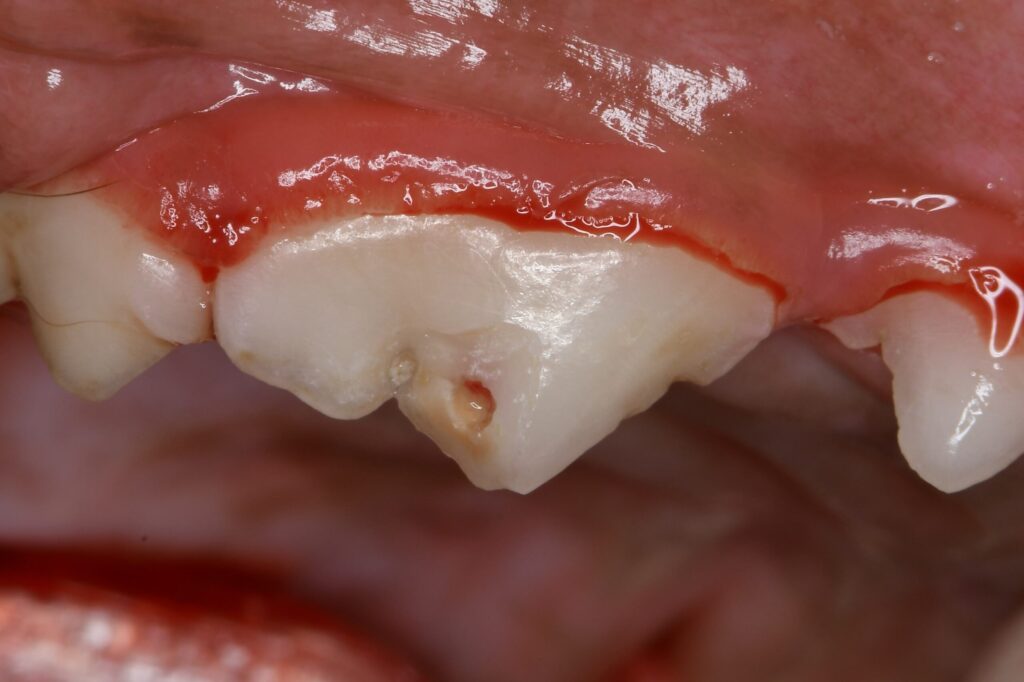

ヒヅメやアキレスなどを与えて歯が折れる子が少なくありません。

不用意に硬いおもちゃも与えないようにしましょう。

治療後